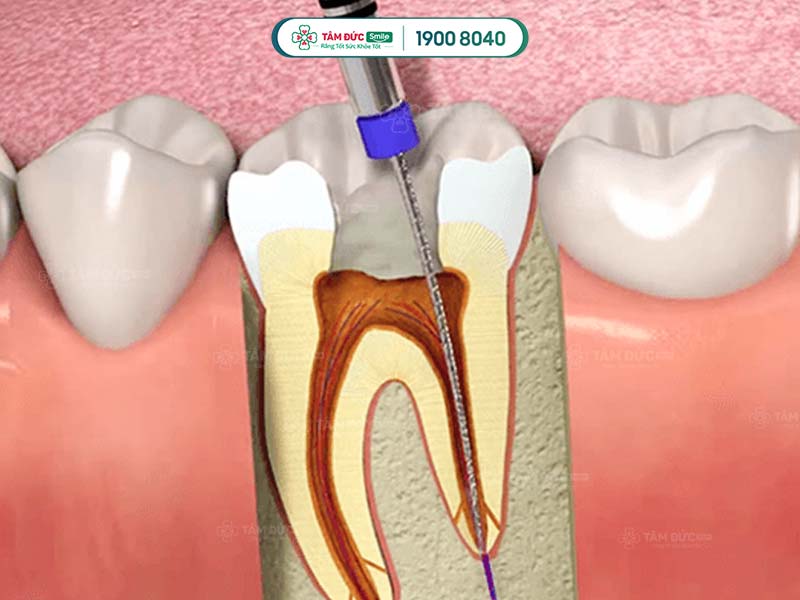

Điều trị tủy hay còn gọi là chữa tủy răng là phương pháp điều trị phổ biến trong nha khoa. Phương pháp này giúp loại bỏ những phần mô đã bị chết hay hoại tử, viêm nhiễm ra khỏi ống tủy. Sau đó sẽ tiến hành trám bít lại bằng những dụng cụ chuyên dụng. Đây được xem là cách làm giảm cảm giác đau đớn, bảo tồn mô răng và tủy hiệu quả.

Chữa tủy răng là một quá trình đổi hỏi thao tác tỉ mỉ, cẩn thận cùng với kỹ thuật cao. Thông thường, việc lấy tủy răng sẽ được tiến hành thông qua 4 bước cơ bản dưới đây:

- Bước 1: Tiến hành thăm khám và đánh giá mức độ tổn thương của răng. Bác sĩ sẽ chụp X-Quang để kiểm tra mức độ tiêu xương răng và các phần bị khuất trong ống tủy.

- Bước 2: Thực hiện gây tê để làm giảm cảm giác đau cũng như ê buốt cho bệnh nhân.

- Bước 3: Khoan răng để đưa dụng cụ lấy tủy vào bên trong khoang miệng. Tiến hành việc lấy tủy răng bằng dụng cụ chuyên dụng cho tới khi ống tủy được làm sạch.

- Bước 4: Tạo hình cho ống tủy và tiến hành trám bít lại bằng miếng trám chuyên dụng.

Điều trị tuỷ răng qua 4 bước cơ bản